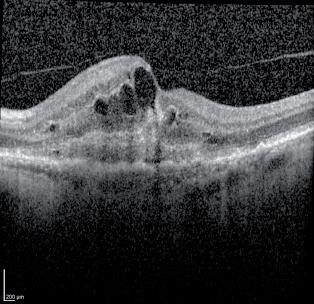

1.12 Nález na předním segmentu u sestřenice; a) pravé oko, b) detail na zadní embryotoxon, c) detail zdůrazňující hypoplazii duhovky, d) řez komorovým úhlem pomocí optické koherenční tomogra e dokumentující adherence pruhů duhovky k zadnímu povrchu rohovky